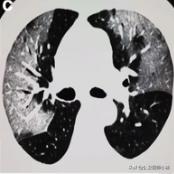

肺实变和结节

肺结节

中心结节周围毛玻璃样改变

中心结节、周围毛玻璃样改变

根据感染的不同程度累积一个或多个肺叶